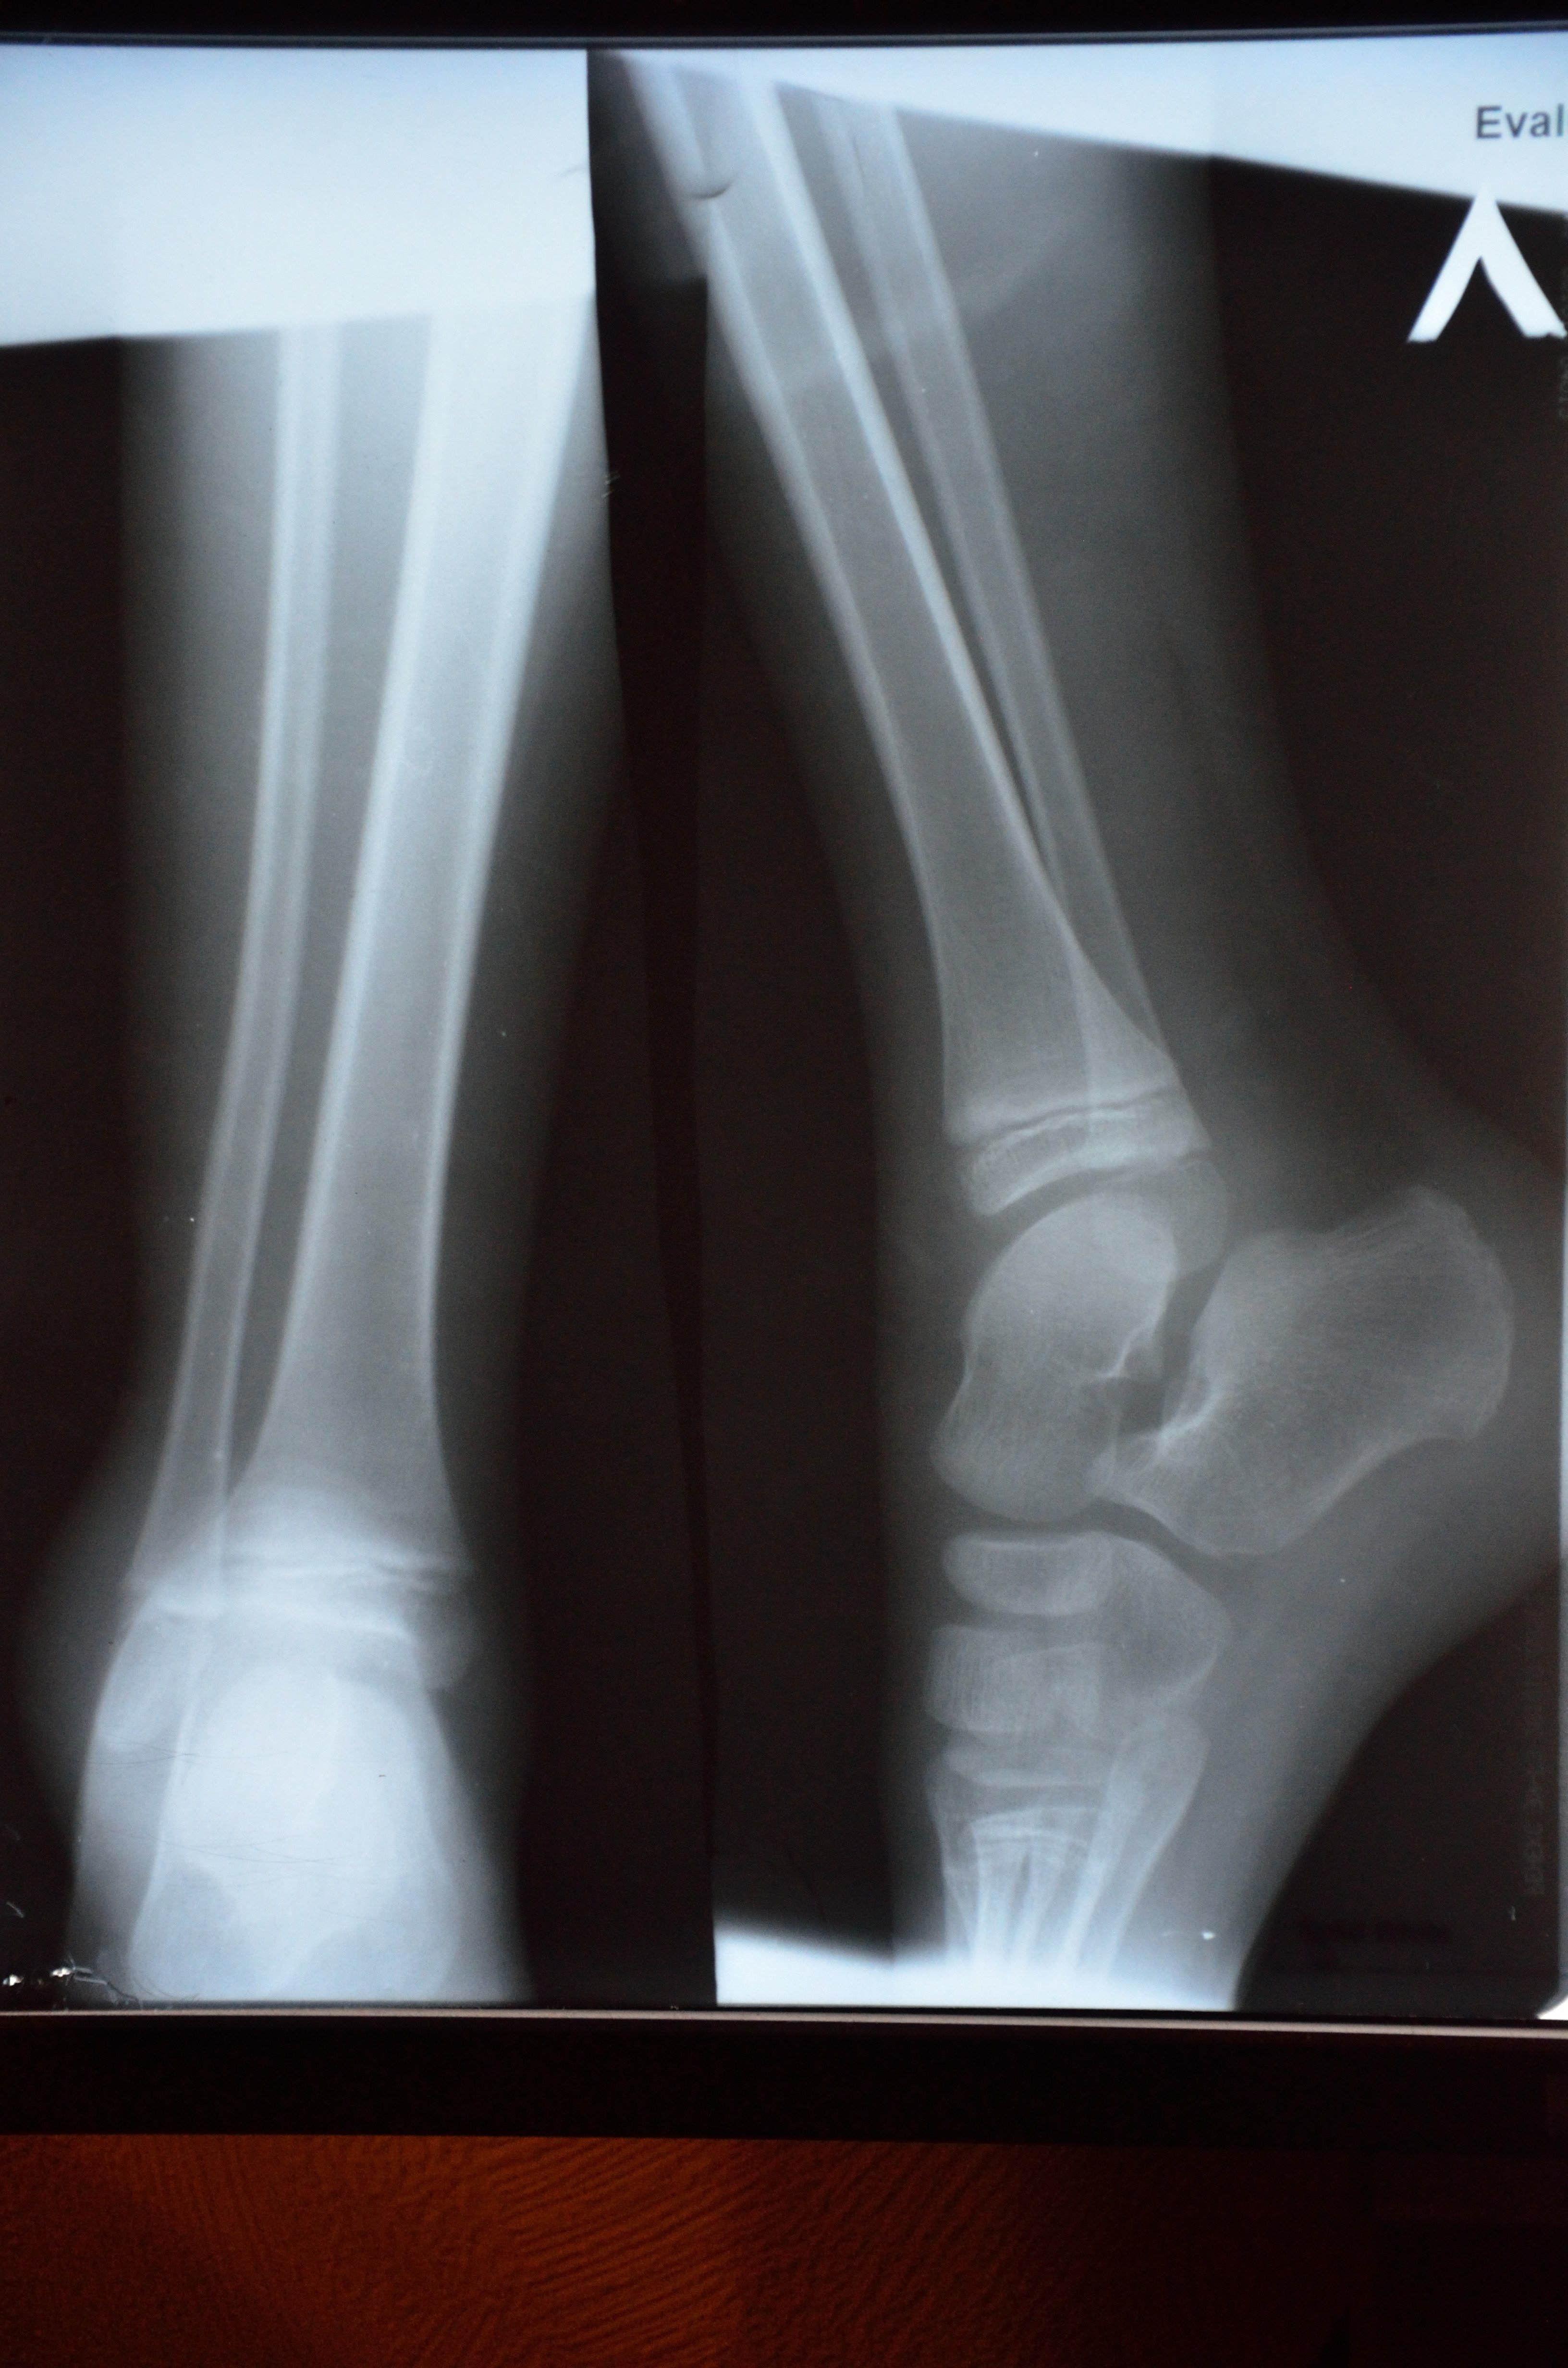

Травма голеностопа. Ребёнок 7 лет

Требуется помощь. Ребенок в деревне, врачей нет. Снимок кое-как сделали, наложили гипс. Есть ли специалисты, понимающие в снимках детских костей? К спецам по взрослым костям уже обращались.